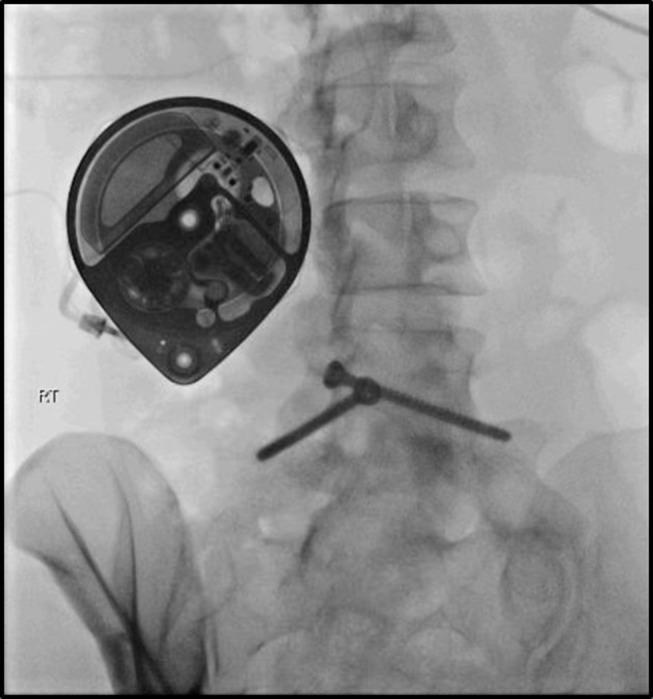

在患有癌症相关疼痛的患者中,10%至20%的患者按照世界卫生组织的三阶梯指南无法实现充分控制。因此,对于这些病例,有人建议采取包括介入治疗方法在内的“第四步”。系统评价支持早期使用介入程序来治疗难治性癌症疼痛、控制症状并防止阿片类药物剂量增加。有强有力的证据表明腹腔神经丛或内脏神经松解术、椎体成形术、后凸成形术和鞘内药物递送的有效性。已发现这些程序与症状负担减轻和阿片类药物消耗减少、生活质量改善相关,并且被认为对生存可能有积极影响。几项研究建议在更早阶段使用特定的介入技术,甚至可能在首次考虑阿片类药物治疗时就使用。相反,将这些选择留作最后的镇痛资源可能并不可取,因为这些程序可能给病情过重的患者带来的负担很大。本综述的目的是收集已发表的关于使用介入治疗难治性癌症疼痛的现有证据,特别关注比较早期与晚期适应症。检索结果显示专门针对这个问题的文章数量和质量都非常低。证据数量稀少,无法进行系统分析。本文提供了关于在疾病早期将介入技术纳入临床指南的潜在益处的详细叙述性描述。

The Unmet Need for Intrathecal Drug Delivery Pumps for the Treatment of Cancer Pain in England: An Assessment of the Hospital Episode Statistics Database.英国治疗癌症疼痛的鞘内药物输送泵未满足需求:对医院入院统计数据库的评估。

Neuromodulation. 2020 Oct;23(7):1029-1033. doi: 10.1111/ner.13264. Epub 2020 Sep 18.

5

Initiation of Intrathecal Drug Delivery Dramatically Reduces Systemic Opioid Use in Patients With Advanced Cancer.鞘内给药的启动显著减少了晚期癌症患者的全身性阿片类药物使用。

Neuromodulation. 2020 Oct;23(7):978-983. doi: 10.1111/ner.13175. Epub 2020 May 27.